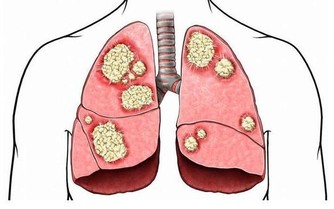

中醫認為一切病先是神病,然後是氣病,再到血病,最後才到什麼呢?形病。疾病先從生命無形的部分,即從精神、信息的層面開始出問題;第二個階段,到氣的部分,能量格局和運行規律發生紊亂;第三個階段,到有形的疾病層面。很多人的病,其源頭是某種很大的煩惱、很大的怨恨,或者很多他們無法解決的困惑。很多時候,病是因為他們不願意去面對、澄清、解決。

這段話大家慢慢思考,為什麼現在病越來越多,越來越不好治,可以從這裡找原因。一切的源頭,在於無形的思想、精神,然後才有了能量,然後才化生為物質。

所有的病,都是這麼來的。